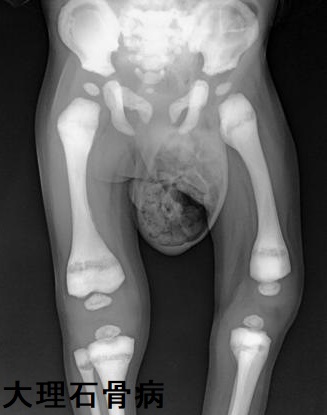

大理石骨病(marble bone disease)は破骨細胞の異常により一次性骨梁(石灰化軟骨)が吸収されず残存する病態。一次性骨梁(石灰化軟骨)は

- 全身の骨硬化

- 骨髄腔狭小により造血障害

に至ります。

大理石骨病の破骨細胞は副甲状腺ホルモン(PTH)に対する反応が悪いものの、血清副甲状腺ホルモン(PTH)、カルシトニンは正常。

大理石骨病患者の骨組織では破骨細胞数が増加。[J Bone Joint Surg Am. 1980 Apr;62(3):384-99.]

大腿骨頭滑り症を合併した大理石骨病と先天性甲状腺機能低下症の報告があります。[Endocr Pract. 2010 Jul-Aug;16(4):646-9.]

(写真;Radiopaediaより改変)